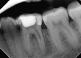

Case 2: A 52-year-old female referred to the clinic for the treatment of tooth 21. Intra-oral examination showed a poor restoration on tooth 21. Percussion and palpation were negative with mobility grade 1. Radiographic examination showed an unsatisfactory restauration on tooth 21 with an apical radiolucency. After obtaining the written consent, the treatment was carried out. The area was anesthetized. Tooth was isolated using the rubber dam and access cavity was opened.

The root canal used for shaping was the EdgeTaper Blaze Utopia to size F2 #25. The final irrigation protocol was performed by a continuous delivery of EDTA and NaOCl. Solutions were activated using ultrasonic activation - 1 minute per solution. Canals were dried and obturated using hydraulic condensation with EdgeBioCeramic Sealer (EdgeEndo).

Lateral and secondary canals are visible on the post operative radiograph.

Pre-op

Post op

One year follow up